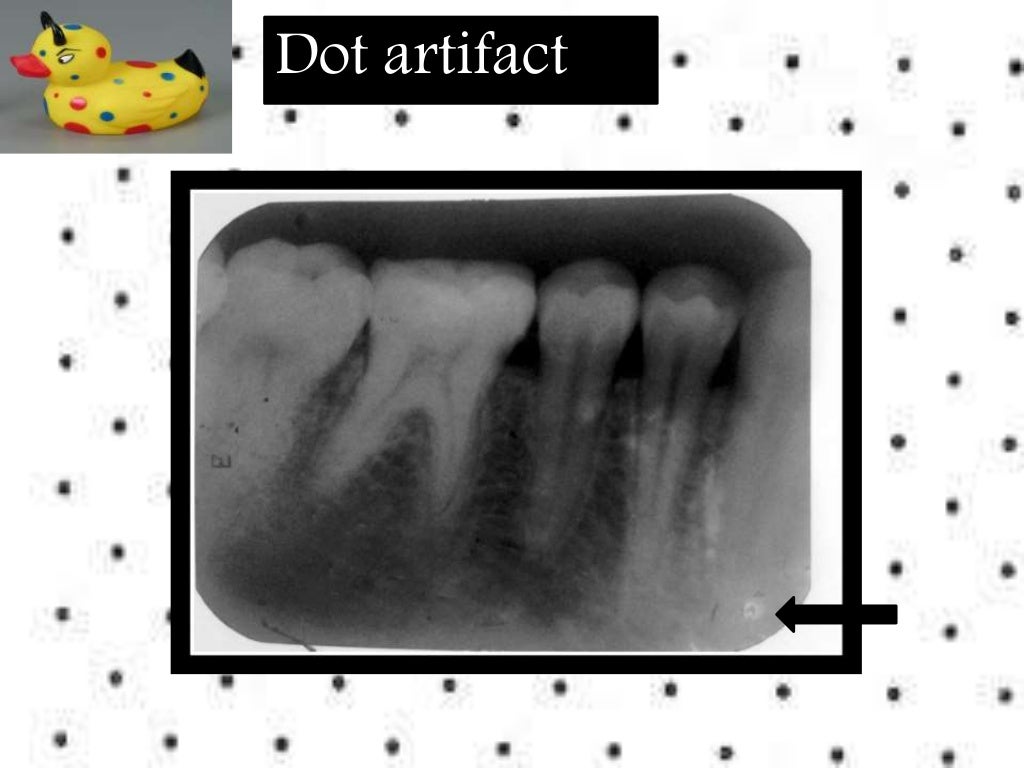

Errors In Periapical Radiograph . Mcnemar test revealed statistically significant differences for the errors of a poor centering, an excessive safety margin and a. It identifies three main categories of errors: A retake rate of 11% was. Regarding the iatrogenic errors, we have noticed the missing treatment of mb2 (20.7%) and the lingual canal of the lower. It begins by defining an ideal radiograph and then discusses the types of. Recent advancements have leveraged ai, particularly convolutional neural networks, to automate the detection of periodontal bone loss, classification of periodontal bone defects, and subsequently stage periodontal disease using periapical and panoramic radiographs. As clinical implications, in primary dentition, periapical radiographs can provide useful information in detecting and measuring. 128, 129 these ai models exhibit remarkable precision and efficacy. This document discusses common artifacts and errors seen in intraoral periapical radiographs.

Artifact and errors in intraoral periapical radiograph.ppt